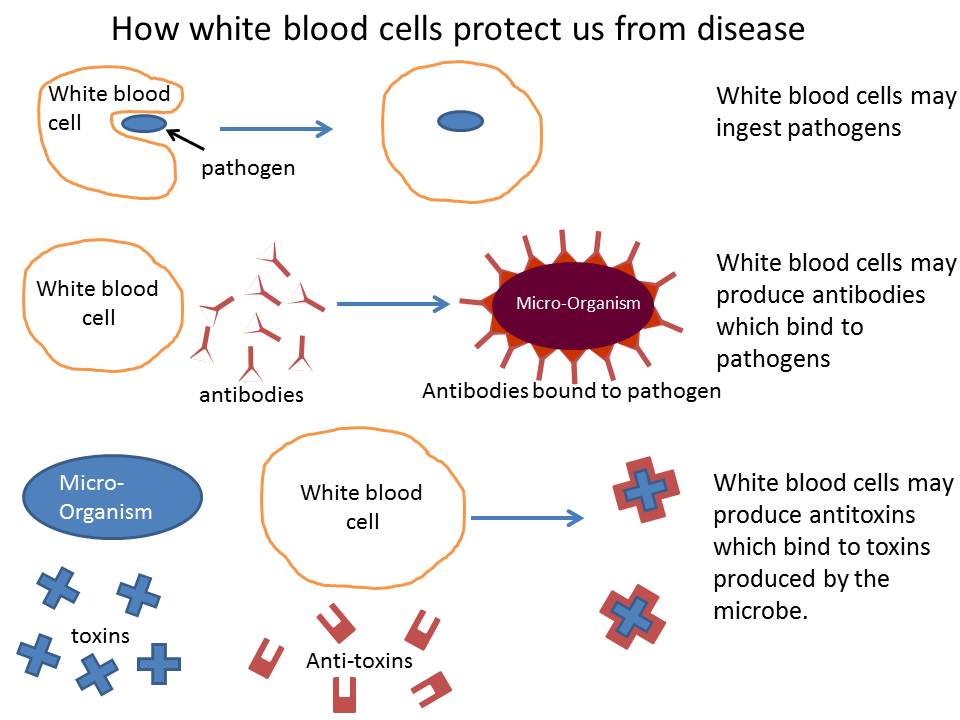

- Components of blood and their functions (Red blood cell, white blood cell, platelets and plasma (blood groups)